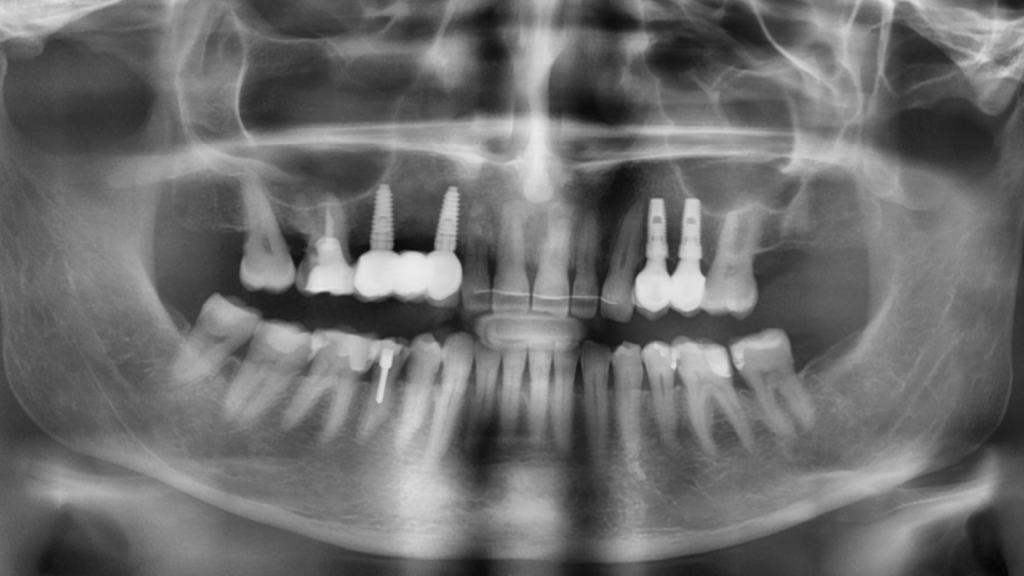

Одномоментная имплантация Impro с установкой временного абатмента

Описание клинического случая:

• Атравматичное удаление зуба 2.4, 2.5

• Одномоментная дентальная имплантация IMPRO

• Использование фибриновой мембраны Clot-PRF

• Установка временного абатмента IMPRO

• Изготовление индивидуального формирователя десны

Клинический случай Узденовой Зульфы Альбертовны